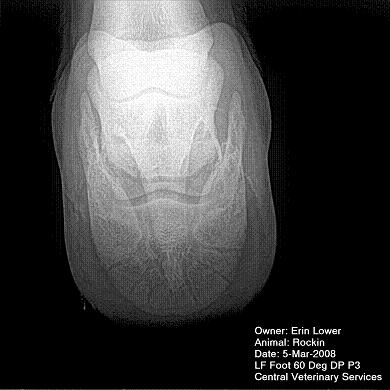

So, Rockin's x-rays were sent to a radiologist and he confirmed "normal" changes in the navicular bones for a horse her age, but slightly more significant ones in the right (sore) foot.

She also has sidebone in both fronts, but apparently that isn't causing any discomfort.

Finally, she has a "small chronic exostosis on the lateral aspect of the proximal phalanx" which, according to the radiologist, shouldn't be causing discomfort but I have read that these can be mild-to-moderately painful... I wouldn't mind another opinion on that.

I will attach as many images as possible from her x-rays (there are many different views). I don't have any pics of the feet as someone deleted them from my camera before I could download them. I'll try to take pics next time she is trimmed. Please, anyone with knowledge of hooves, give any opinions that you might have (especially Dr. O!)

I cannot rule out lesions based on these images but I will take your radiologist's word that he does not see significant lesions. The exostosis on the RF would be above the level of a well conducted PDN which I believed blocked the lameness before?